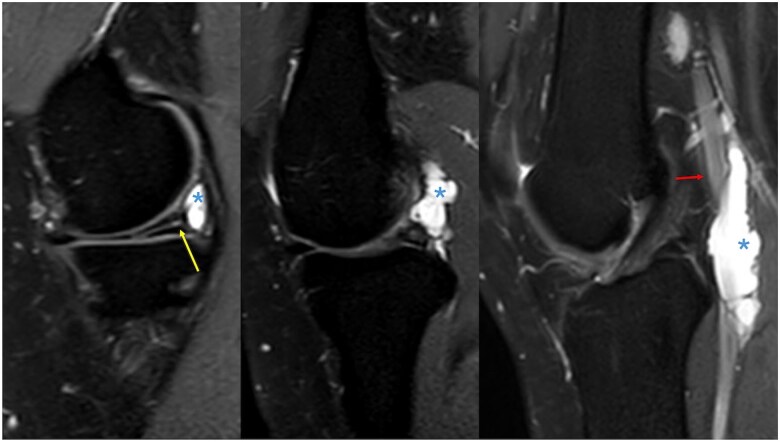

囊性外膜病是一种罕见的小腿跛行原因,其特征是在动脉外层(外膜)内发生粘液囊性肿块。腘动脉最常受影响。关于这种疾病的病因存在几种理论和假设,迄今为止文献中没有明确的统一原因。我们描述了一个32岁的女性病例,她有一年的右膝内侧疼痛和间歇性跛行史,她被诊断为内侧半月板撕裂和一个与腘动脉外膜相连的大腹膜旁囊肿。她接受了关节镜半月板切除术和囊肿减压,并获得了良好的功能结果,跛行得到了解决。

Cystic adventitial disease is a rare cause of calf claudication and is characterized by the development of a mucinous, cystic mass within the outer layer (adventitia) of an artery. The popliteal artery is most commonly affected. Several theories and hypotheses exist regarding the aetiology of this disorder with no clear unifying cause accepted in the literature to date. We describe a case of a 32-year-old female with a one-year history of medial right knee pain and intermittent claudication who was diagnosed with a medial meniscal tear and a large parameniscal cyst communicating with the popliteal artery adventitia. She underwent arthroscopic meniscectomy and cyst decompression and achieved an excellent functional outcome with resolution of the claudication.